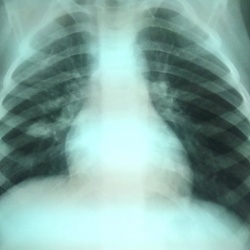

Молодой пациент 1994 г.р. Никогда не болел. Ничего не болит и ничего не беспокоит. Профилактическая флюорография. Что бы это значило?